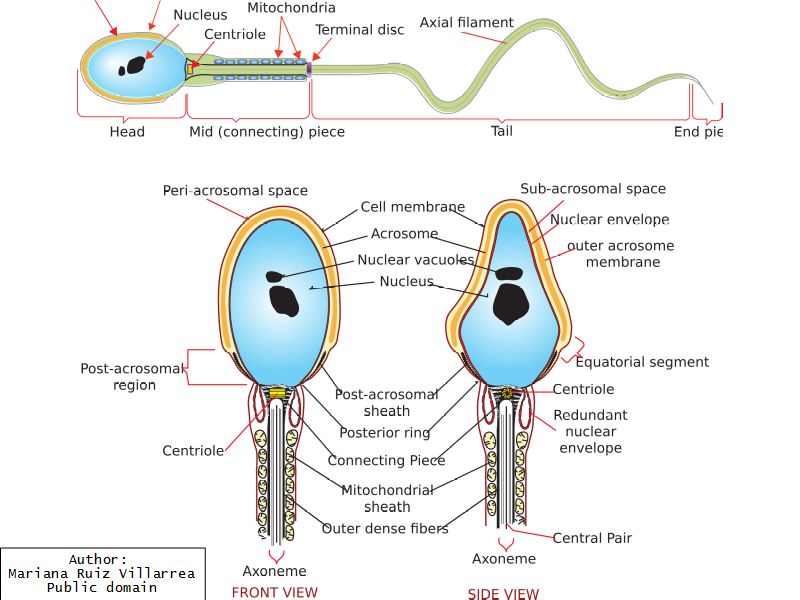

Spermatozoa

- Head

- Contains nucleus

- Dense chromatin

- Acrosomal cap anterior over nucleus

- Midpiece

- Mitochondrial sheath

- Small amount cytoplasm

- ATP for flagellar motility

- Tail

- Principle piece

- End piece

- Microtubuli for movement